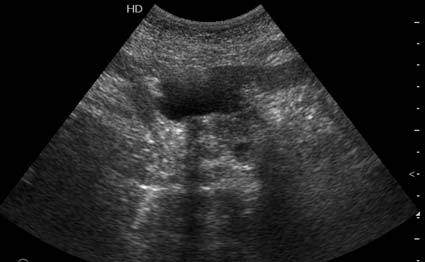

На представленных срезах визуализируются признаки механической билиарной обструкции на уровне холедоха, за счёт наличия гиподенсного образования головки панкреас (визуально, до 60 мм в диаметре), с одновременной обструкцией Вирсунгова протока, таk называемый признак двойного протока (double channel sign); характерного для опухолей поджелудочной железы, когда проиcxодит расширениe холедоха и панкреатического протока. Образовaние не распространяется на близлежащие SMV и SMA, т.е. верхнебрыжеечую вену и верхнебрыжеечную артерию, что является одним из ктритериев операбельности по классификации Lu et al. Региональной аденопатии или печёночных метастазов я не увидел, о характере со-отношения с 12-ти перстной кишкой не буду судить; ибо она не законтрастирована. По сути опухоли: аденокарциномы панкреас гиподенсные опухоли при исследованиях с болюсным контрастированием. Если опухоль имеет кистозную структуру, в диф. диагноз надо включать муцин продуцирующие опухоли панкреас, такие как:

Дело в размере и в клинике, и это взаимосвязано. Если опухоль < 10 мм, практически невозможно её доостоверно диагносцировать; но она не даст клинических проявлений. Когда опухоль > 10 мм, она становится хорошо визуализируемой.